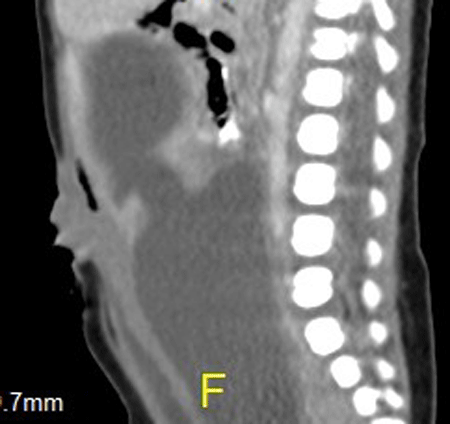

A female newborn, a product of consanguineous marriage born by caesarian section delivery with a birth weight of 3.75 kg, was admitted to our hospital with abdominal distension. Antenatal ultrasound showed congenital heart disease and a pelvic mass. On examination, she had lower abdominal mass emanating from the pelvis. There was polydactly and syndactly of the right hand and polydactly of the right foot. There was also an anterior ectopic anus. Cardiovascular work up revealed common atrio-ventricular (A-V) canal with single atrium, moderate patent ductus arteriosus and severe A-V regurgitation. Abdominal ultrasound and CT-scan showed hydrometrocolpos with bilateral hydronephrosis and left perinephric fluid collection (Fig. 1). Surgery revealed hydrometrocolpos secondary to a low vaginal atresia. An abdomino-perineal vaginal pull through was performed. Post-operative period was uneventful.

It is important to define anatomic abnormality leading to the hydrometrocolpos. We found CT-scan valuable in this regard. MRI has been reported to be more valuable than ultrasound and CT-scan in delineating the vaginal anatomical defect and the hydroureter and hydronephrosis [2]. Genitography is an unnecessary invasive investigation that may be harmful leading to secondary infection with subsequent pyometrocolpos. Pyometrocolpos which is a serious complication calls for early and rapid evaluation and treatment of these patients. Hydrometrocolpos secondary to vaginal atresia is treated with abdomino-perineal vaginal pull through as we did in our case.

Figure 1: CT-Scan showing hydrometrocolpos. Note the dilated vagina and uterus. |